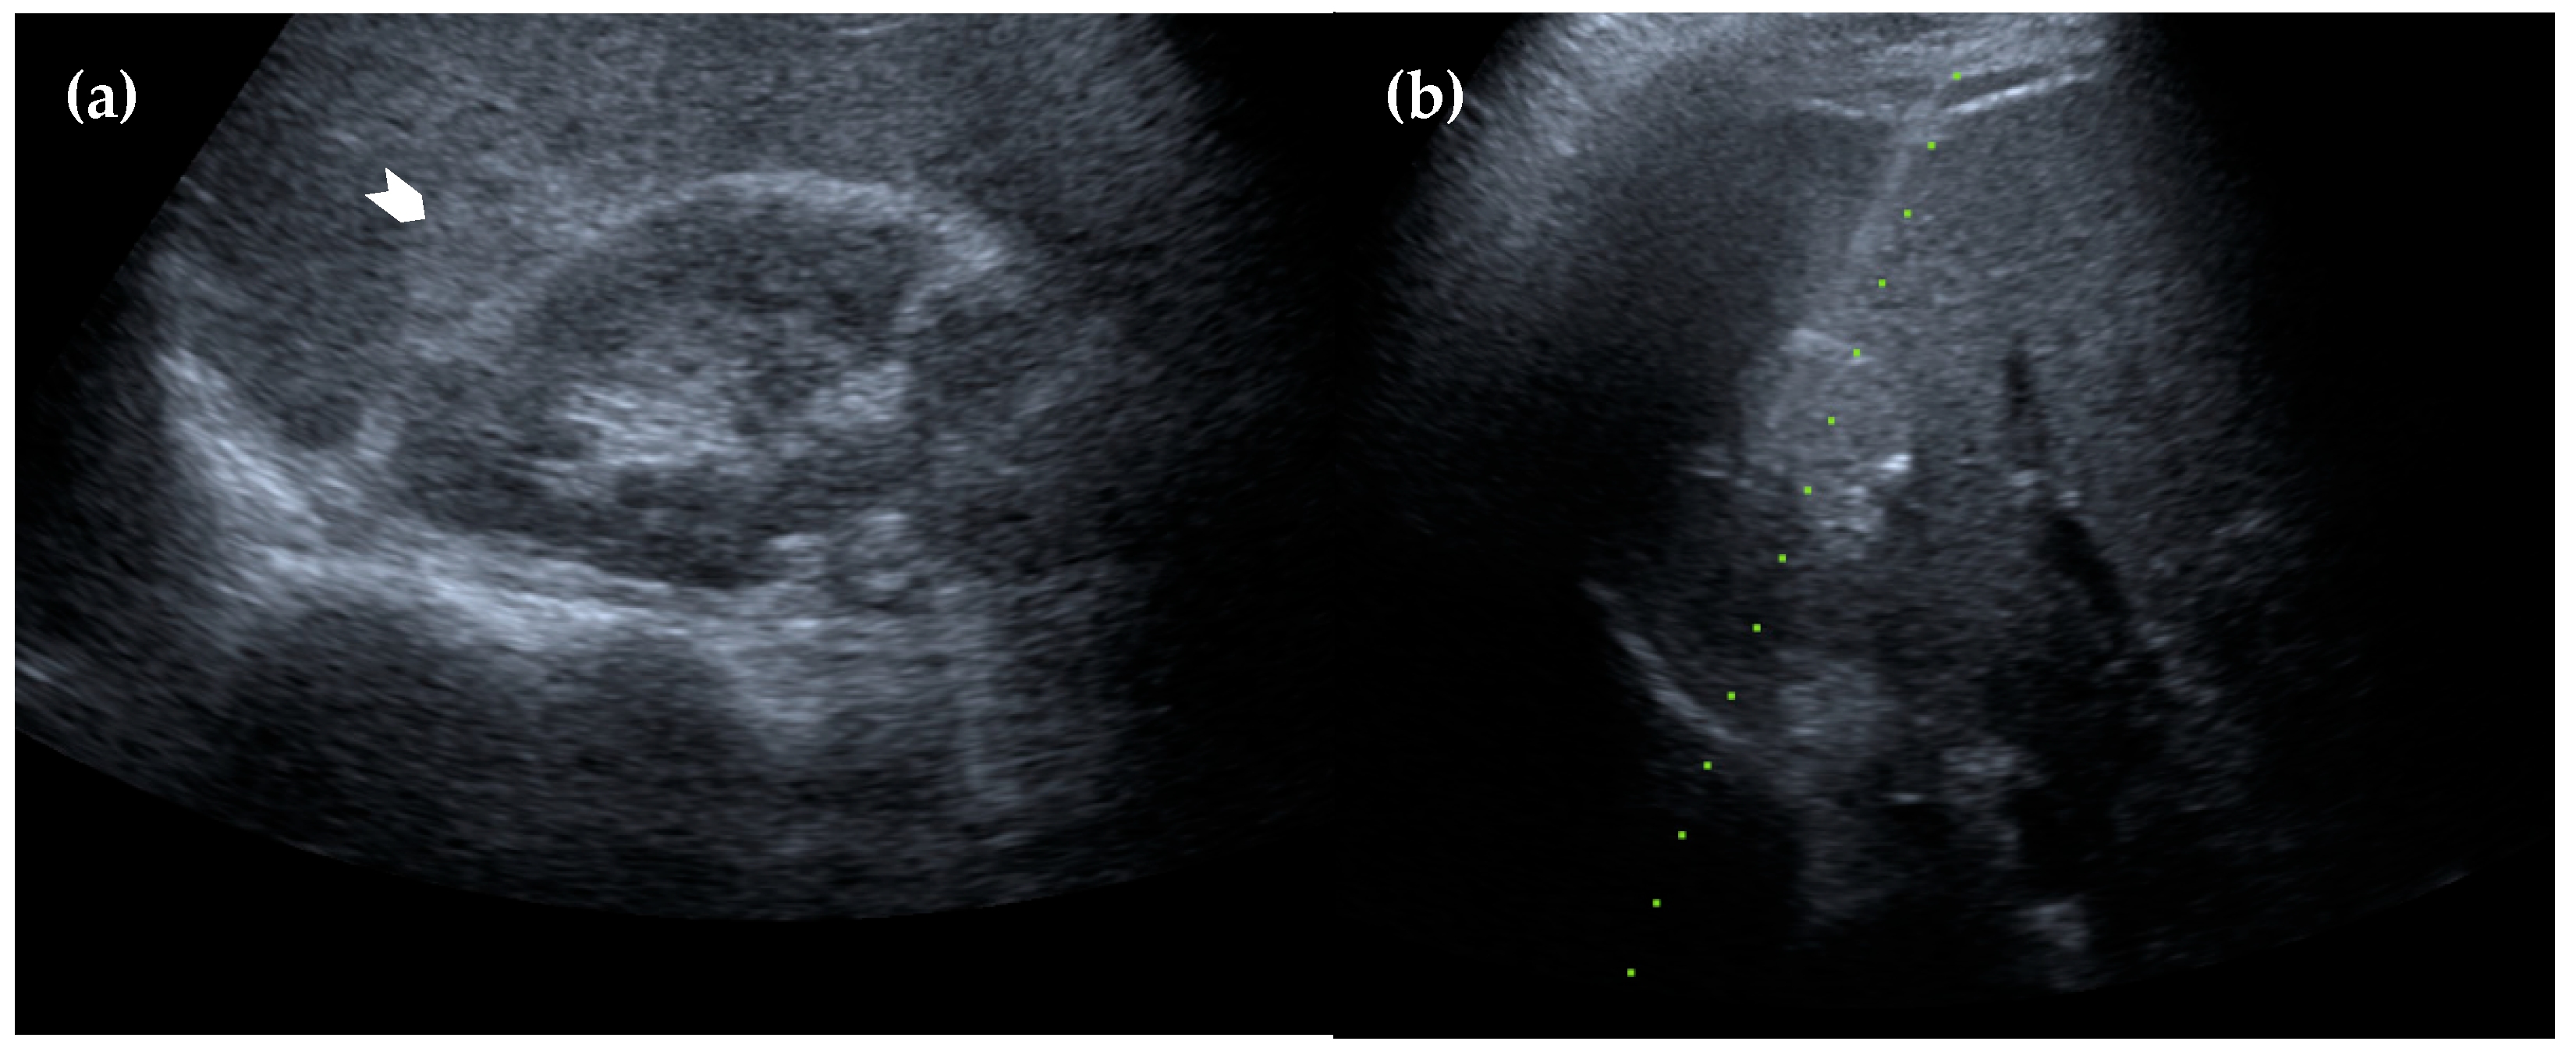

Figure 2. Magnetic resonance imaging of the liver. (a) Axial view of the T1 sequence, in which the intrahepatic lesion is hypointense in comparison to surrounding normal hepatic parenchyma (black arrowhead); (b) axial view of the T2 sequence, in which the lesion is nearly isointense (white arrowhead); (c) coronal view of the T2 sequence. The suspected perinephric splenosis (red arrowhead) again exhibits similar attenuation to the intrahepatic lesion (white arrowhead in (d) and black arrowhead in (e)), as well as characteristics of restricted diffusion on diffusion-weighted imaging (d) and the corresponding apparent diffusion coefficient map (e). These findings support the diagnosis of intrahepatic splenosis [2].